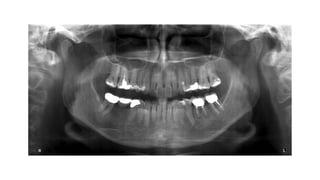

Pros & Cons •Pros • General & rapid assessment of the teeth and facial bones • Low dose of radiation • Cons • Low resolution • Artifacts

Indications • General dentalhealth evaluation for caries or pulp origin disease • Trauma assessment for tooth or jaw fractures • Infection evaluation of sinusitis, periodontitis or periapical disease • Tumour or radicular cyst evaluation • Temporomandibular joint assessment for disease. • Foreign body localization • Salivary stone identification • Growth and development monitoring of paediatric teeth for location, shape, angle, supernumerary tooth, • Initial and progressive evaluation of orthodontic treatment